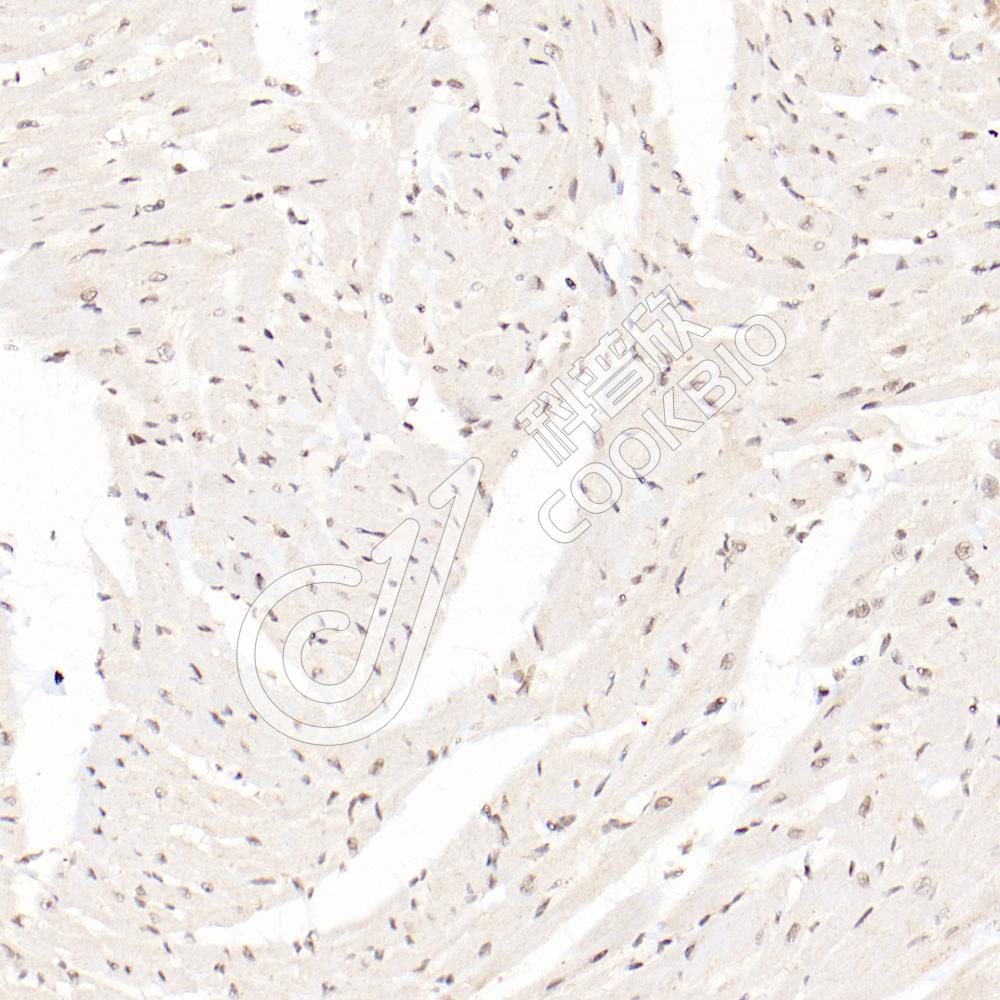

IHC检测USP13蛋白(货号 K1335004).

样品: 大鼠心, 4%多聚甲醛 (货号KSG1101) 固定12-24小时.

抗原修复: 柠檬酸抗原修复液(干粉, pH 6.0) (KSG1201), 98℃, 20分钟.

—抗: 1: 1000稀释, 4℃ 孵育过夜.

二抗: S-vision免疫组化多聚二抗(山羊抗兔),即用型 (货号KB3906), 室温孵育20分钟.